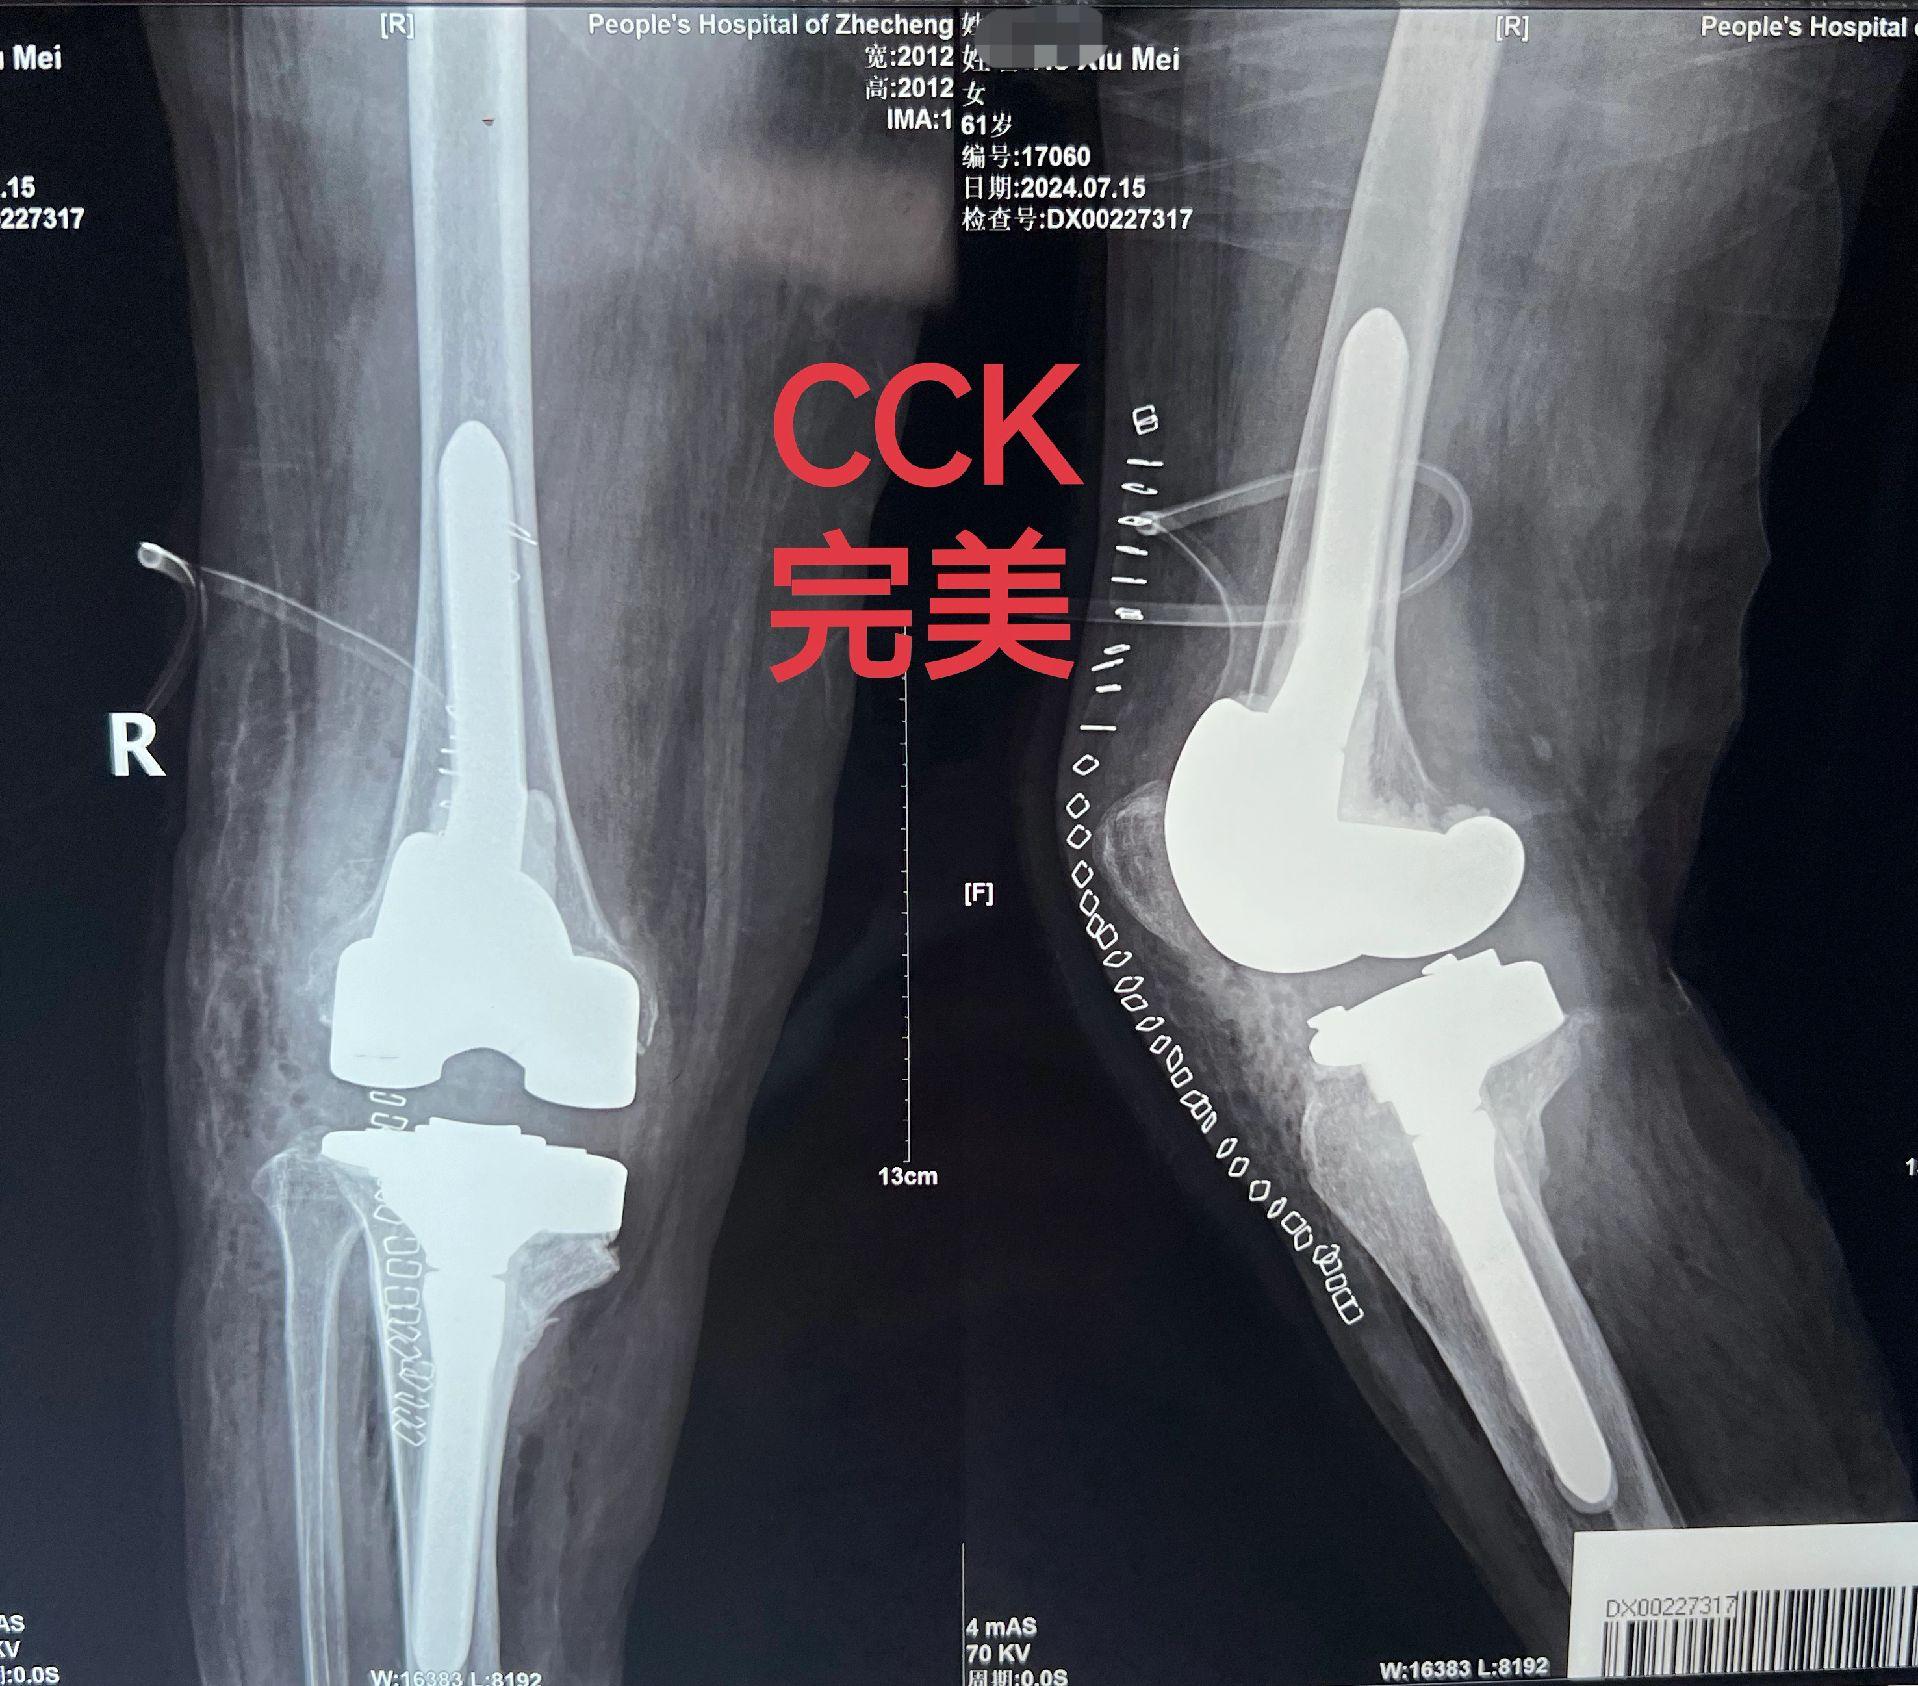

类风湿关节炎。类风湿关节炎,关节毁损,无法行走。备的CCK和铰链膝,最终CCK完美解决。用最小的代价给患者带来最大的获益🌹